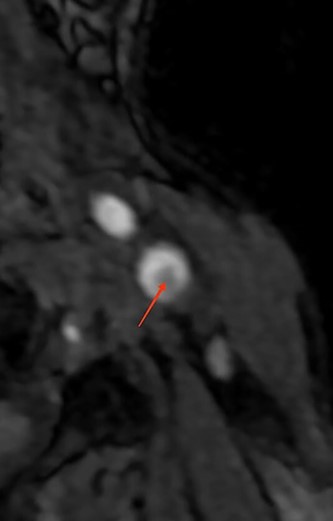

| • Supra-aortic trunks and cerebral arteriography: typical aspect of carotid diaphragm | • Supra-aortic trunks echo Doppler + agioscanner: carotid diaphragm with floating thrombus of the right carotid artery(Fig. 1) | • MRI and supra-aortic trunks angiogram: carotid bulb thrombus (Figs 2 and 3) | • Angioscanner: very suggestive of carotid diaphragm |

A thrombus found rostral to the carotid diaphragm is described in 12–29% of case series [7].